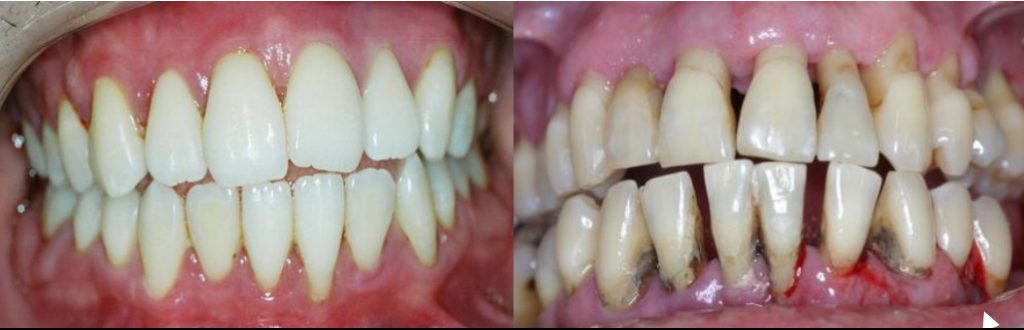

- Cirurgias e Regeneração (em casos específicos): Se a doença já causou perda óssea significativa, pode ser necessária uma intervenção cirúrgica. Isso pode envolver desde um simples retalho na gengiva para acessar melhor a raiz, até técnicas de regeneração óssea com enxertos ou membranas.

Intervenção Cirúrgica e Regenerativa

Se a periodontite já avançou e causou danos sérios ao osso que sustenta os dentes, a cirurgia pode ser a saída. Existem técnicas que buscam